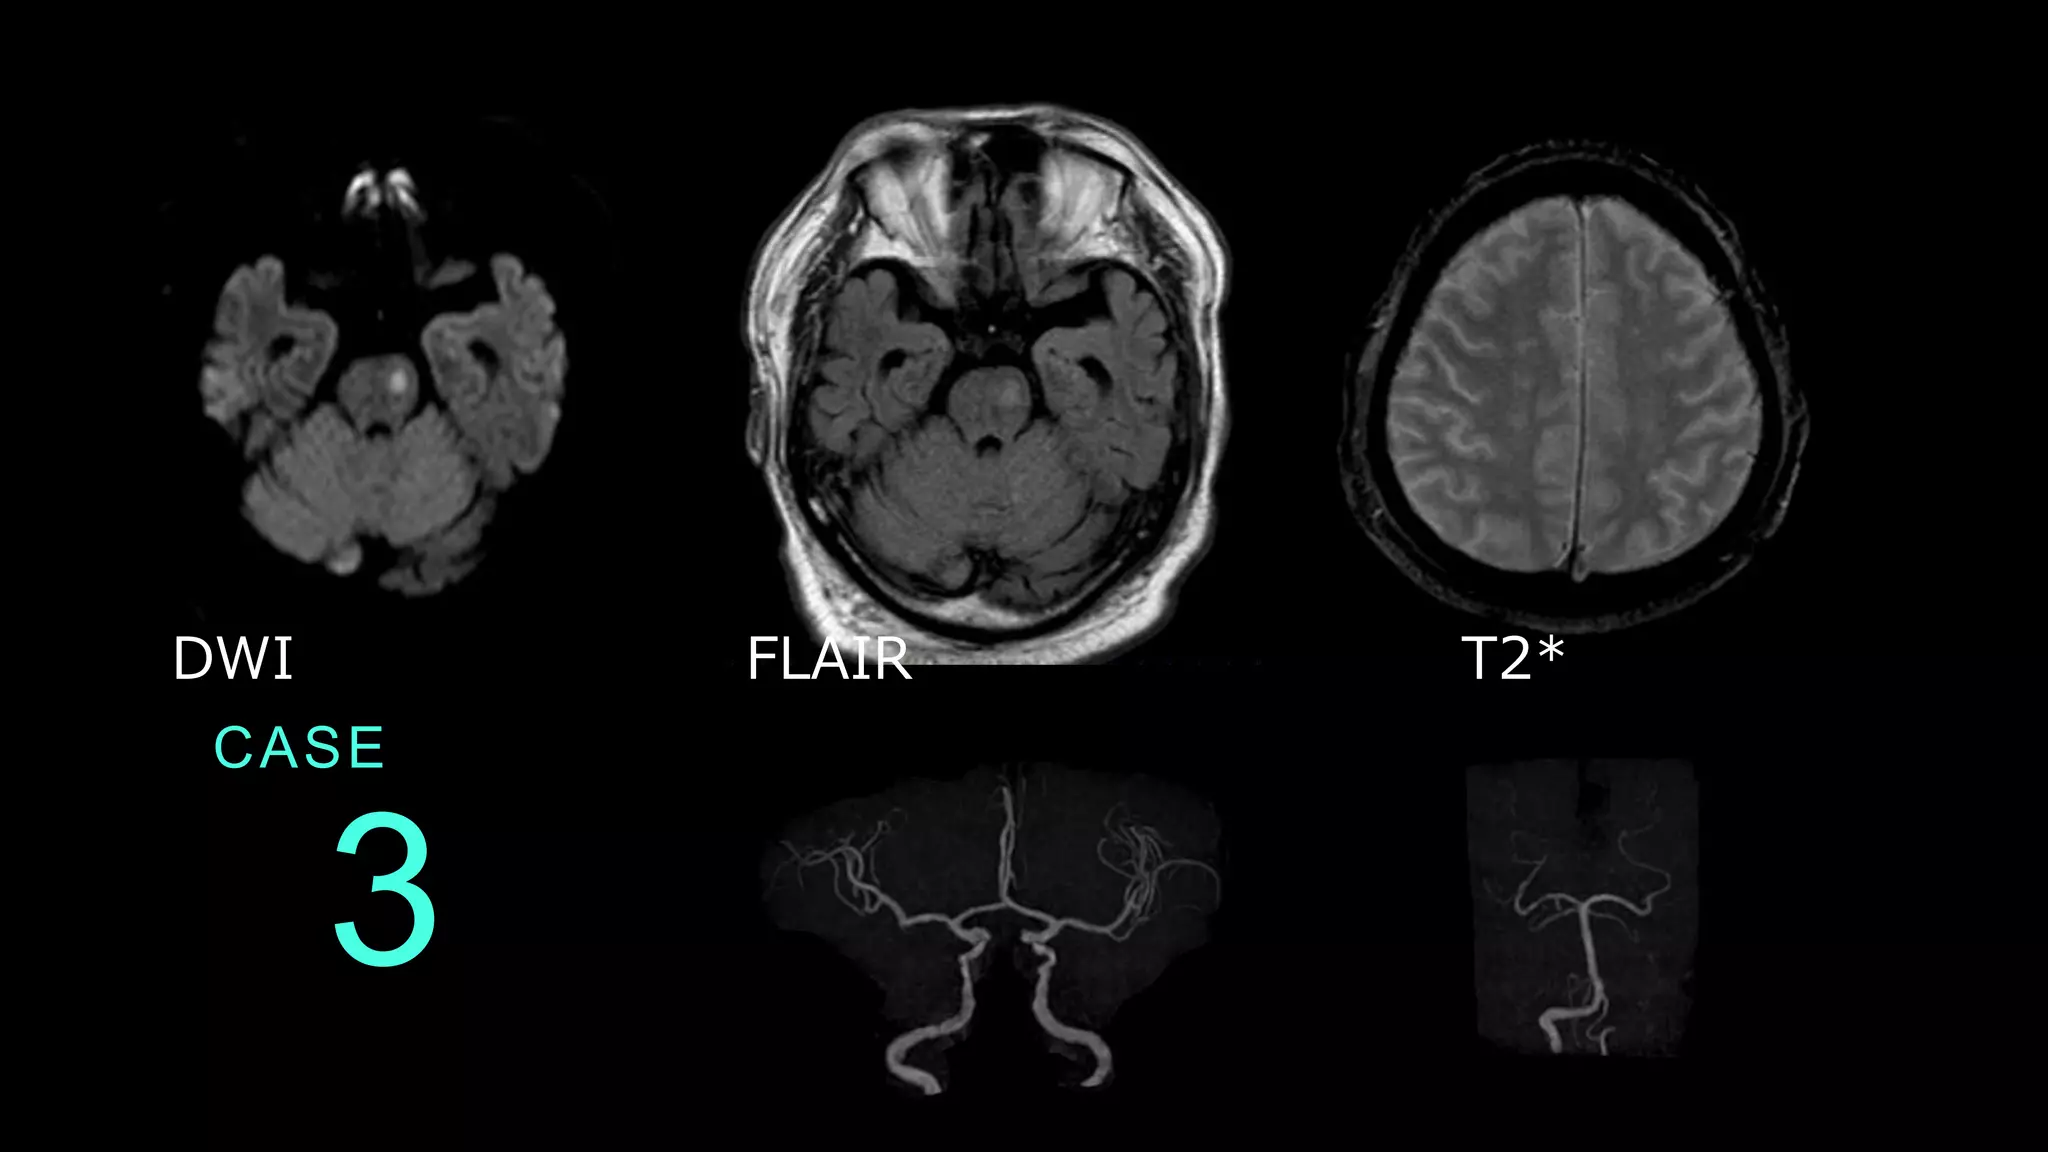

CASE 3 DWI FLAIR T2*

CASE 3 DWIでは左側の脳幹に高信号病変を認める。 同病変は、FLAIRではやや高信号を呈している。

CASE 3 MRAでは前方循環系はICAの口径不整が認められる。 後方循環系は、左のVAが右より細く描出されている。

CASE 3 コメント: 脳幹のラクナ梗塞。DWI HIGHでFLAIRもHIGHなので、 やや時間のたった病変であることがポイントです。 なお、左VAは先天的な低形成と推測されます。